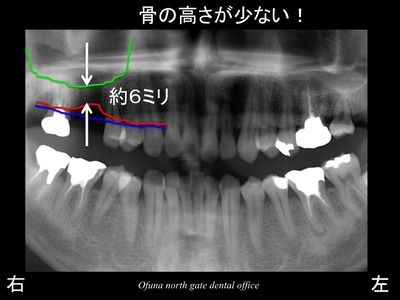

いつものように 骨吸収の状態を分かりやすくするために

骨吸収の状態を線で書いたのが以下のレントゲンになります。

青線が骨吸収を起こす前の骨の位置です。

赤線は、現在の骨の位置です。

骨吸収が起こっているのが分かるかと思います。

次に問題となるのが上顎洞の存在です。

緑線は上顎洞という空洞です。

緑線の上方は、骨ではなく、穴が開いているのです。

骨もない、ただの空洞です。

骨吸収が起こっていることと 上顎洞の存在により

インプラントを埋入するための骨の高さが少ないのです。

具体的には、骨の高さが約6ミリ程度しか存在していません。

上顎の奥歯に適切な長さのインプラントを埋め込むためには、

10ミリ以上の長さのインプラントが必要です。

現在の残っている骨の高さは約6ミリということは、

4ミリ以上の骨の高さが不足していることになります。